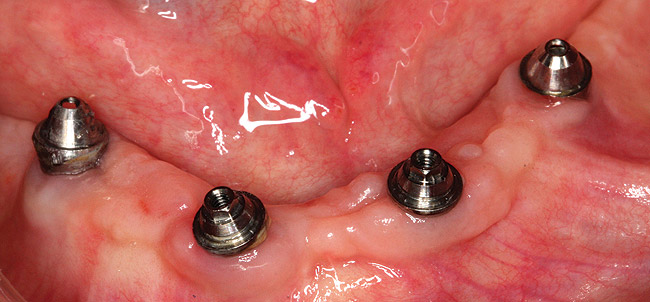

The patient was allowed to heal, and postoperative follow-up treatments were performed until osseointegration was complete (Figure 5 and Figure 6). Three months later, the provisionals were removed and abutment-level impressions were taken for the definitive restoration. Pickup impressions of the provisional prosthesis served as verification jigs and were mounted. While the patient waited for the return of their temporary restorations, tooth selection and shape were discussed, agreeing upon a polymethyl methacrylate acrylic material (PMMA), known for providing long-lasting restorations. While earlier generations of denture teeth were likely to fracture, Mondial® Denture Teeth (Heraeus Kulzer, www.heraeus-dental-us.com) were chosen in this particular case due to their voidless, high-density center specifically designed to accommodate the opening for the insertion of the screw without weakening, for screw-retained prostheses.

Figure 5  Three-month postoperative image of the upper and lower arch implant abutments.

Figure 5

Figure 6  Three-month postoperative image of the upper and lower arch implant abutments.

Figure 6